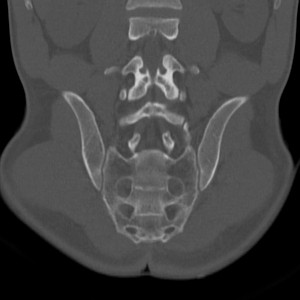

Тазобедренные суставы